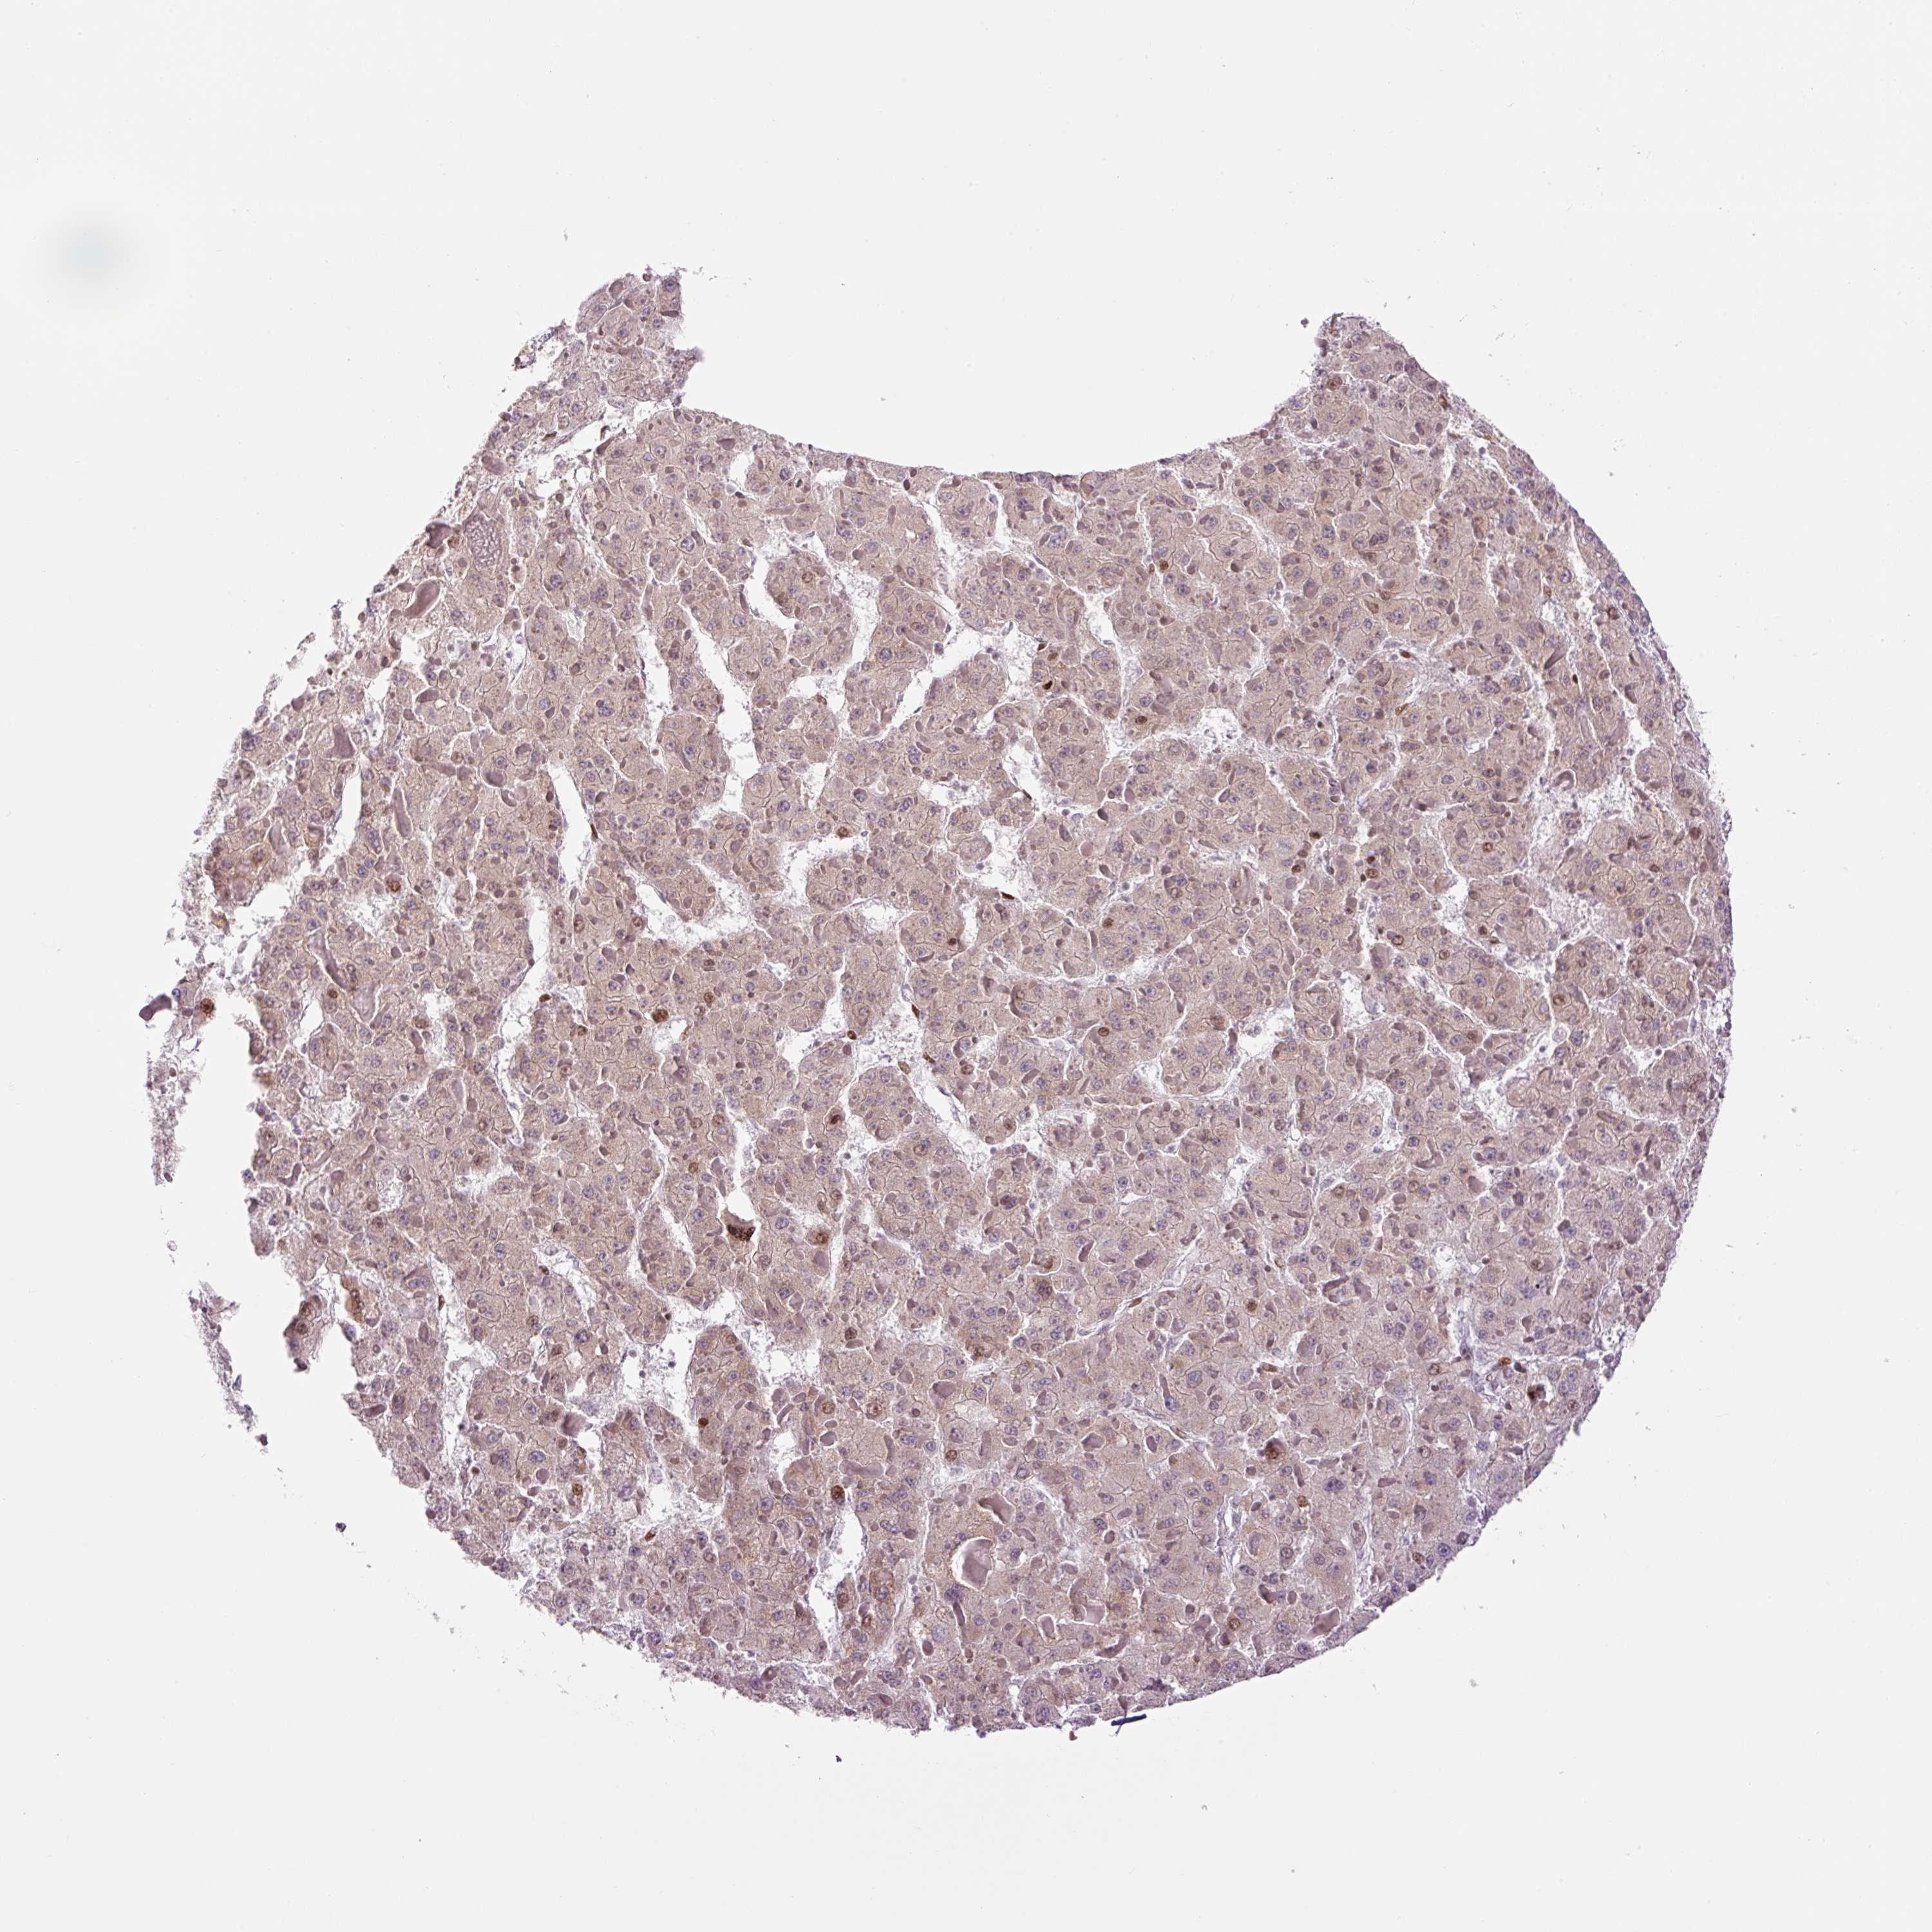

LIVER CANCER - Protein expressioni

A mouse-over function shows sample information and annotation data. Click on an image to view it in a full screen mode. Samples can be filtered based on level of antibody staining by selecting one or several of the following categories: high, medium, low and not detected. The assay and annotation is described here.

Note that samples used for immunohistochemistry by the Human Protein Atlas do not correspond to samples in the TCGA dataset.

Antibody stainingi

Antibody staining in the annotated cell types in the current human tissue is reported as not detected, low, medium, or high, based on conventional immunohistochemistry profiling in selected tissues. This score is based on the combination of the staining intensity and fraction of stained cells.

Each image is clickable and will lead to virtual microscopy that enables deeper exploration of all samples and also displays staining intensity scores, fraction scores and subcellular localization as well as patient and tissue information for each sample.

Antibody HPA053816

Staining

High

Medium

Low

Not detected

Intensity

Strong

Moderate

Weak

Negative

Quantity

>75%

75%-25%

<25%

None

Location

Nuclear

Cytoplasmic/membranous

Cytoplasmic/membranous,nuclear

Carcinoma, Hepatocellular, NOS

Cholangiocarcinoma